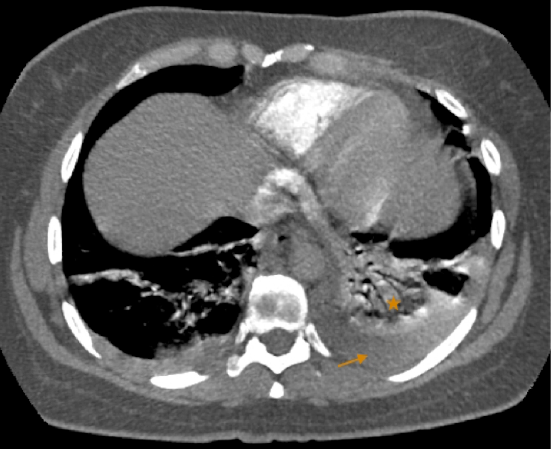

Angiotac aorta torácica y pulmonares 1 Angio 2 Estudio de tórax En primer lugar en una arteria de gran calibre identificamos 3 capas la íntima en contacto con el lumen (calcificaciones), luego la media y la más externa es la adventicia. Snowflake, 4angioTACtrombooclusivopulmonar AngioTAC #, 3 Signo de Westermarck #, img0801 #. Se realizó angiografía por tomografía axial computada (angioTAC) de arterias pulmonares, que demostró TEP bilateral, que comprometía arterias pulmonares principales, con dilatación de VD ( Figura 1 ), y reflujo del contraste hacia la vena cava inferior, hallazgos que indicaban disfunción ventricular derecha.

Sospechar un tromboembolismo pulmonar y proceder a su confirmaciónn • Las mujeres deben ser informada de los posibles efectos adversos de los anticonceptivos y su forma de presentación clínica, para poder detectarlos precozmente. TROMBOEMBOLIA PULMONAR (Clasificación de Wells (< 4 Poco probable 4 TROMBOEMBOLIA PULMONAR, s1q3t3 #, HNF IM forbidden Abscesos Frios!. O AngioTAC TEP radiológicamente masivo con signos de hipertensión pulmonar (aumento calibre arteria pulmonar y dilatación VD) 7 O Se comenta de nuevo con UCI y tras valoración del riesgo, se decide ingreso en Neumología con diagnóstico de TEP bilateral 8.

Introducción Concepto El tromboembolismo pulmonar 1,2 (TEP) es el cuadro clínico que resulta de la obstrucción de la circulación arterial pulmonar de un émbolo procedente del sistema venoso profundo de las extremidades inferiores y de la región pélvica Junto con la trombosis venosa profunda (TVP) constituyen la enfermedad tromboembólica venosa (ETV). AngioTAC es una tomografía axial computarizada con medio de contraste que permite estudiar la circulación sanguínea en las arterias y venas, Episodios de embolia pulmonar;. En la ecocardiografía de control desapareció la hipertensión pulmonar y en la angioTAC pulmonar se resolvieron los trombos intravasculares.